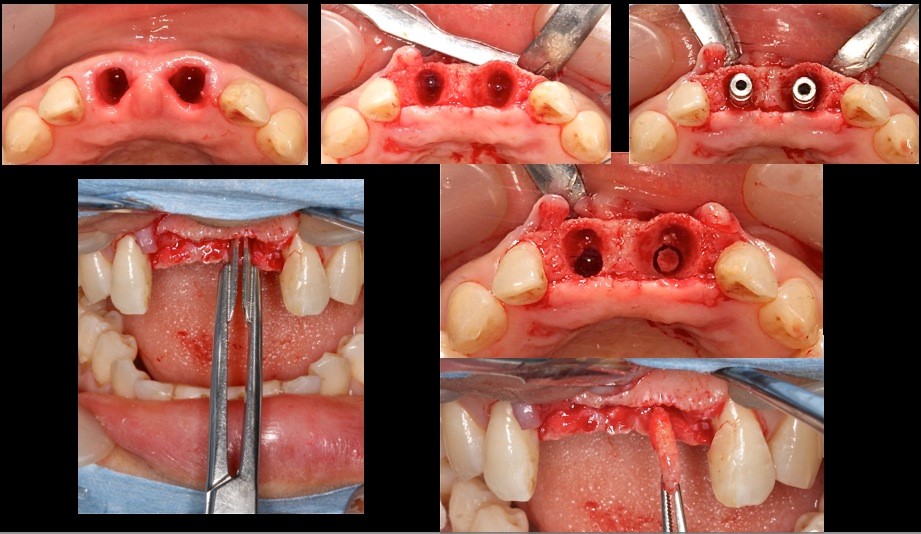

この部位に中切歯2本分の骨尖を砕いて隙間に填塞する 右下の写真で十分填塞できていることが確認できる。

術後3ヶ月 印象時の軟組織の状態

場合によってはフライスドリルで直接骨採取も可能